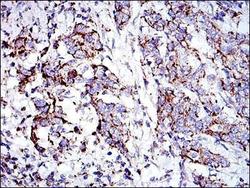

Supportive validation

- Submitted by

- Novus Biologicals (provider)

- Main image

- Experimental details

- Immunohistochemistry-Paraffin: Prohibitin Antibody (5H7) [NBP2-37563] - Immunohistochemical analysis of paraffin-embedded stomach cancer tissues using PHB mouse mAb with DAB staining.

- Submitted by

- Novus Biologicals (provider)

- Main image

- Experimental details

- Immunohistochemistry-Paraffin: Prohibitin Antibody (5H7) [NBP2-37563] - Immunohistochemical analysis of paraffin-embedded rectum cancer tissues using PHB mouse mAb with DAB staining.